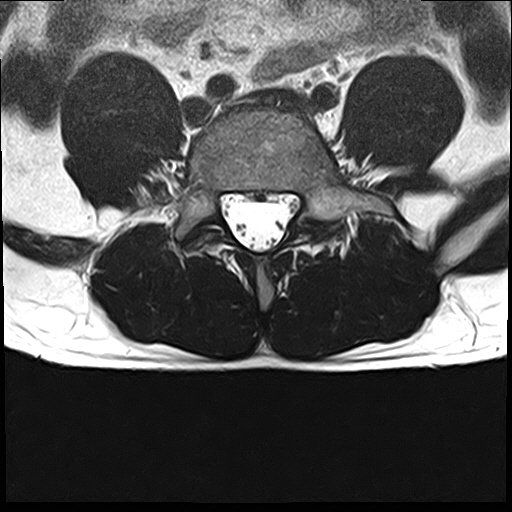

선생님 요추 Mri 판독부탁드립니다 ㅠㅠ

예전 진료에서 척추전방전위증과 그로인한 퇴행성 디스크 그리고 팽윤이 있다고 들었습니다.

현재 제가 디스크가 터진곳이 있을까요?

집근처 병원을 세곳을다니는중인데 어떤곳은 디스크는 멀쩡하다 퇴행성만있을뿐.

어떤곳은 디스크가 터졌다고 하는게 어떤곳이 맞는건가요?

혹시 디스크가 터진게 없다면 통증이 생기는이유는 단순히 척추전방증으로인한 퇴행성디스크와 팽윤 때문인건가요?

디스크가 명확하게 튀어나와 신경뿌리를 압박하는 병변은 보이지 않는 MRI로 생각됩니다.